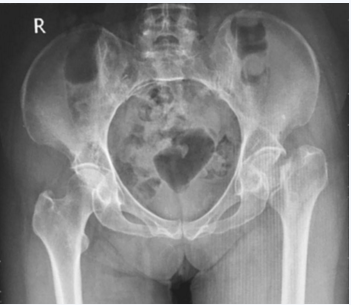

骨盆正位(图1):

图1 骨盆正位片

左股骨颈骨折,移位明显(Garden Ⅳ型)